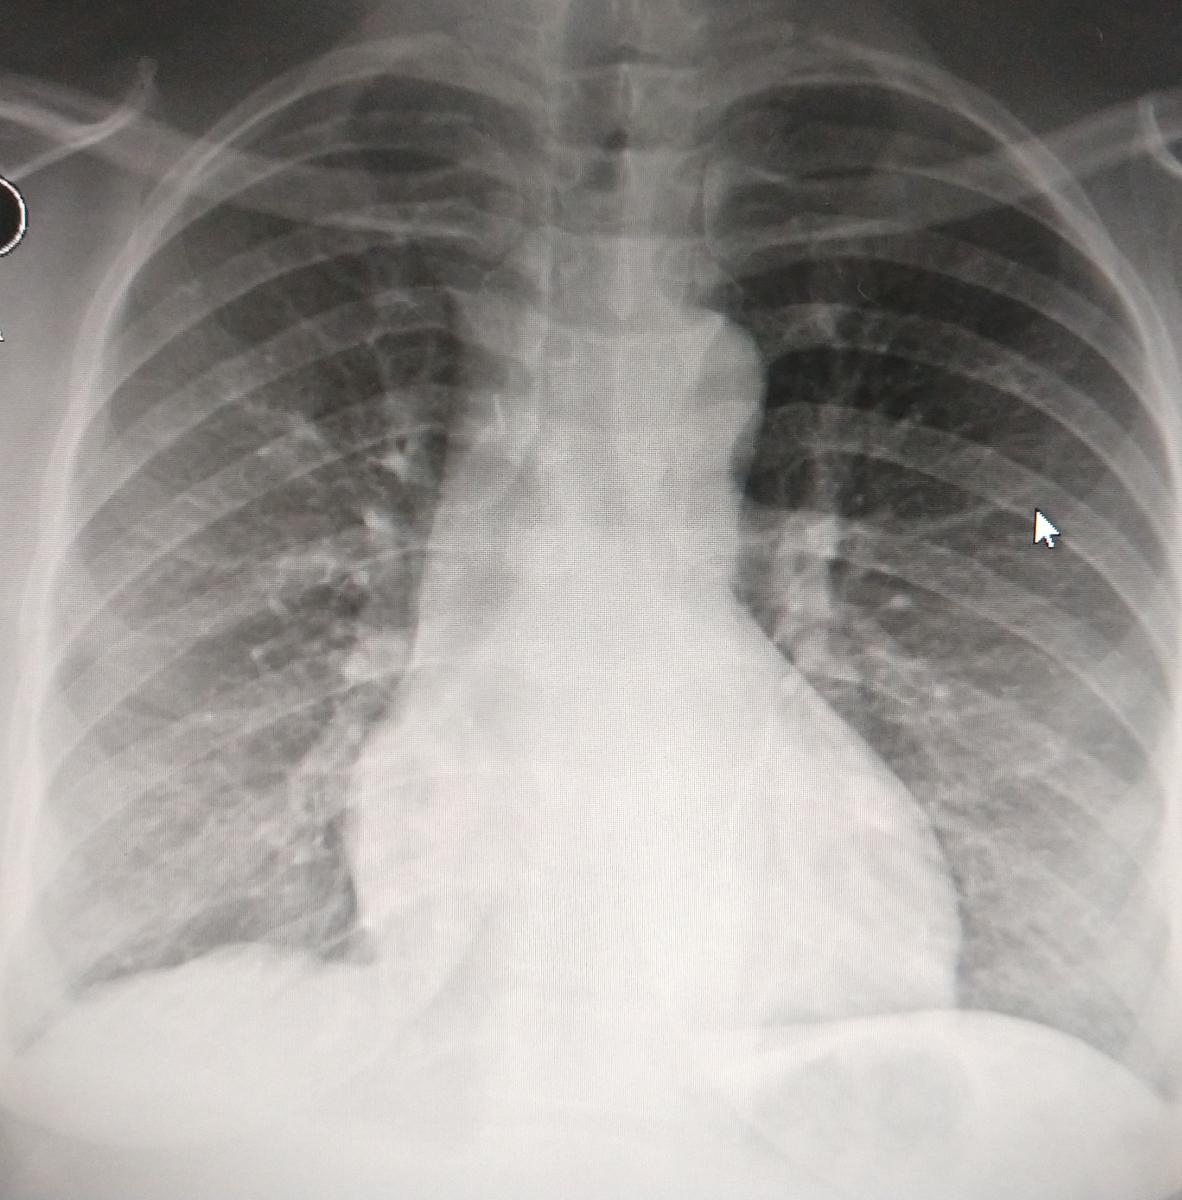

Figure 9. Chest x-ray on the second postoperative day when the patient was discharged. Lungs are fully expanded and no gross abnormality was observed in the operated anterior mediastinum.